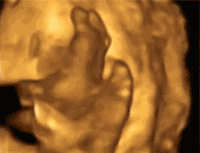

百佳超声影像(四维彩超)

带你走进胎儿的成长地

刻录宝宝珍贵0岁写真

超声影像(四维彩超),运用国际的GE-E8彩超成像设备,立体清晰捕获未来宝宝的及时动态活动图像,为宝宝刻录珍贵0岁写真。